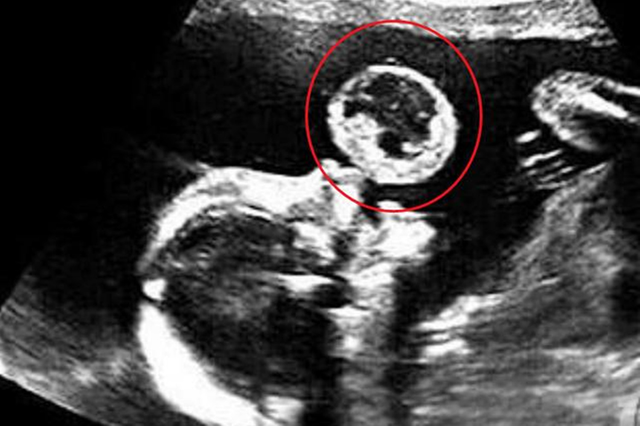

其实是因为,新生儿气管较短,咳嗽反射较差,痰液很难通过咳嗽排出,就会出现口吐白泡来排痰的现象。

但是这个情况仅限于判断新生儿肺炎!

7、吐泡泡 (限于新生儿)